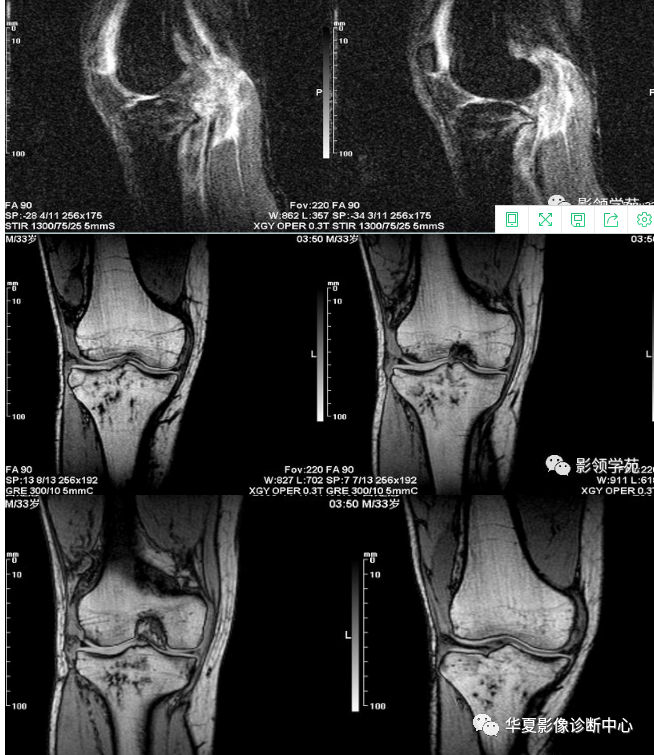

病人术前膝关节核磁,内侧胫骨平台骨挫伤.